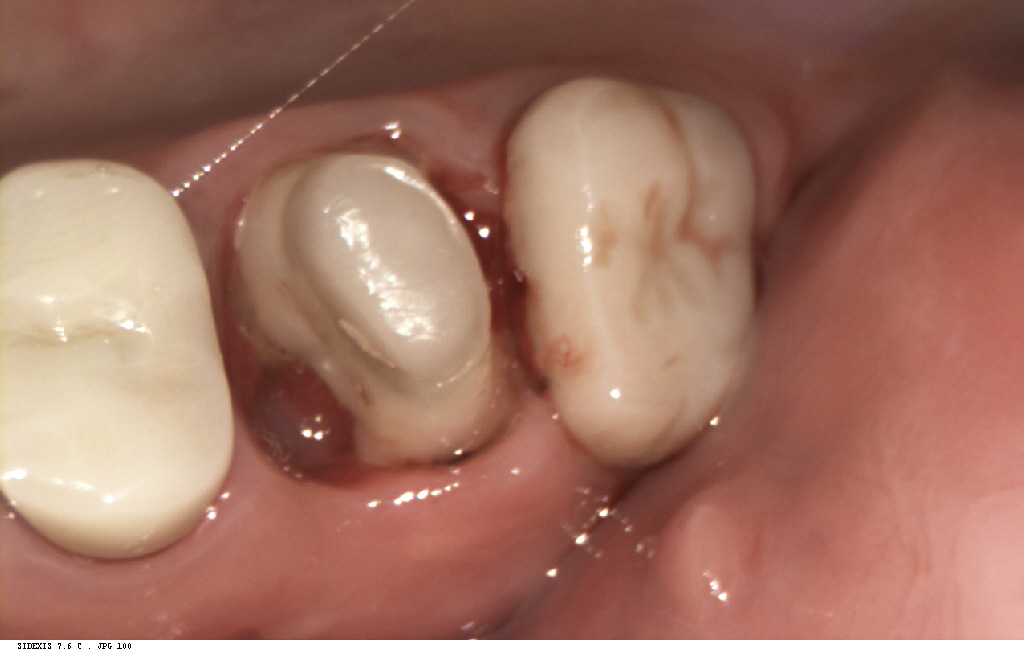

そしてこちらが、治療後の写真です。

見た目だけでなく、

しっかり噛める機能も回復しており、

患者さまにもとても喜んでいただきました。